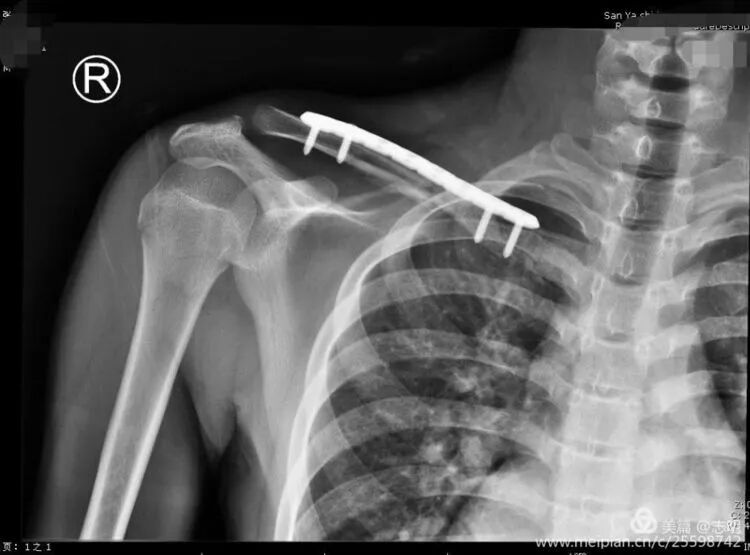

(Post-fixation X-ray). -

(Healed fracture X-ray). -

(Another post-fixation X-ray).

(Post-fixation X-ray showing the plate and screws in place). -